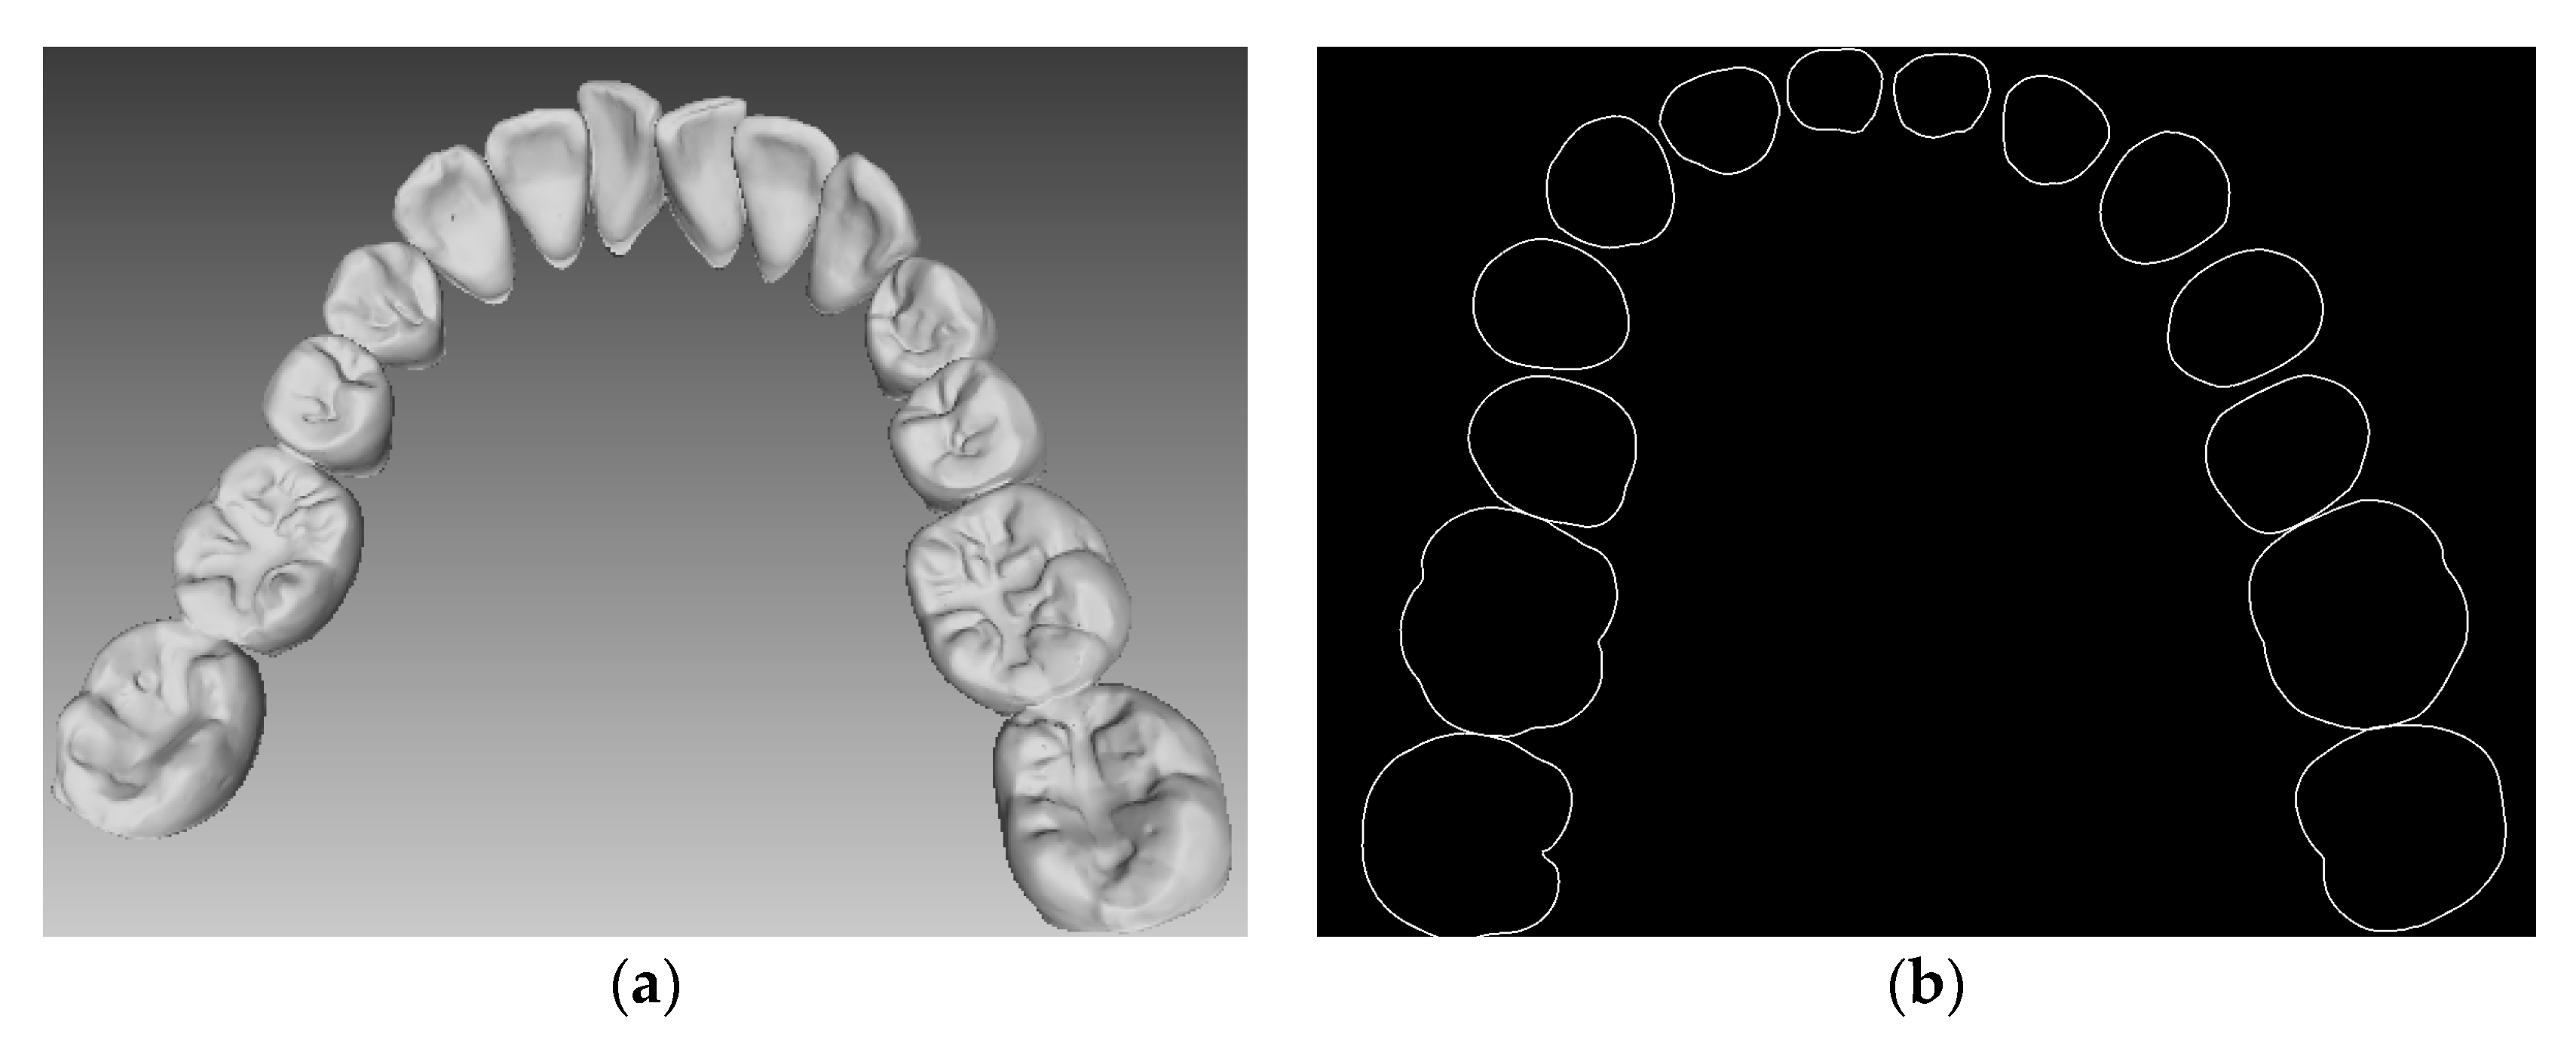

2.2. Reconstruction of Dental Scan Data

3.2.1. Tooth Model

3.2.2. Accuracy Measurement Process